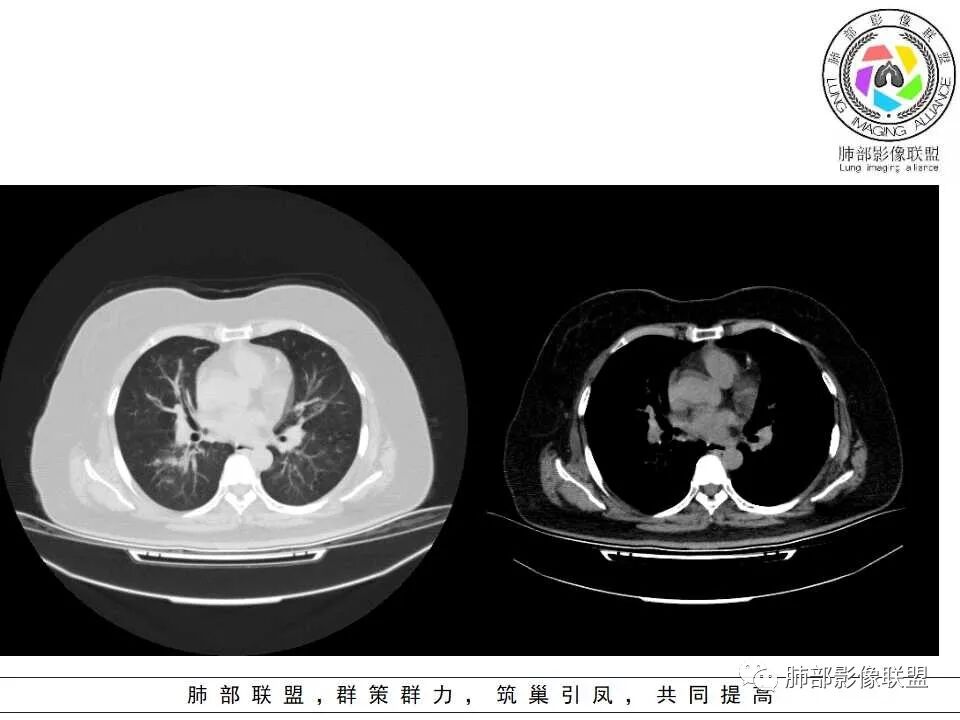

1.器官支气管管套样壁增厚和/或支气管扩张,注意壁增厚较均匀,和/或伴有播散性小片影及结节影,注意这些小片影或结节影边界有时较普通炎性病灶清楚。

2.可以阻塞支气管造成肺不张而酷似中央型肺癌。偶而可呈大范围毛玻璃样影。

二.血管侵袭性肺曲霉病

1.多见于血液恶性肿瘤及造血干细胞移植患者。两肺多发,多见磨玻璃晕,有时病灶基底贴近胸壁形成楔形影。

2.很少支气管壁增厚,也无支气管扩张,少见树芽征。

1.三四级以上支气管显著扩张,柱状扩张为主,常伴痰液嵌塞,远端支气管相对正常,强烈提示ABPA诊断!ABPA的支扩有时来得快去得快。

影像上表现为V形、Y形、葡萄状或指套状阴影,边缘清楚。

2.管腔扩张及管壁增厚(炎性反映),轨道征或环形影常比较显著;

五.寄生型肺曲菌病

曲菌球为寄生性,在空洞性病灶内呈游离状态,呈球形,密度多均匀,偶可高密度,境界清晰,位置可随检查体位而变动。霉菌球与洞(腔)壁之间常留有新月形空隙,形成空气新月征。此为寄生型肺曲菌病的特征性表现。

注意,曲菌球不会强化。